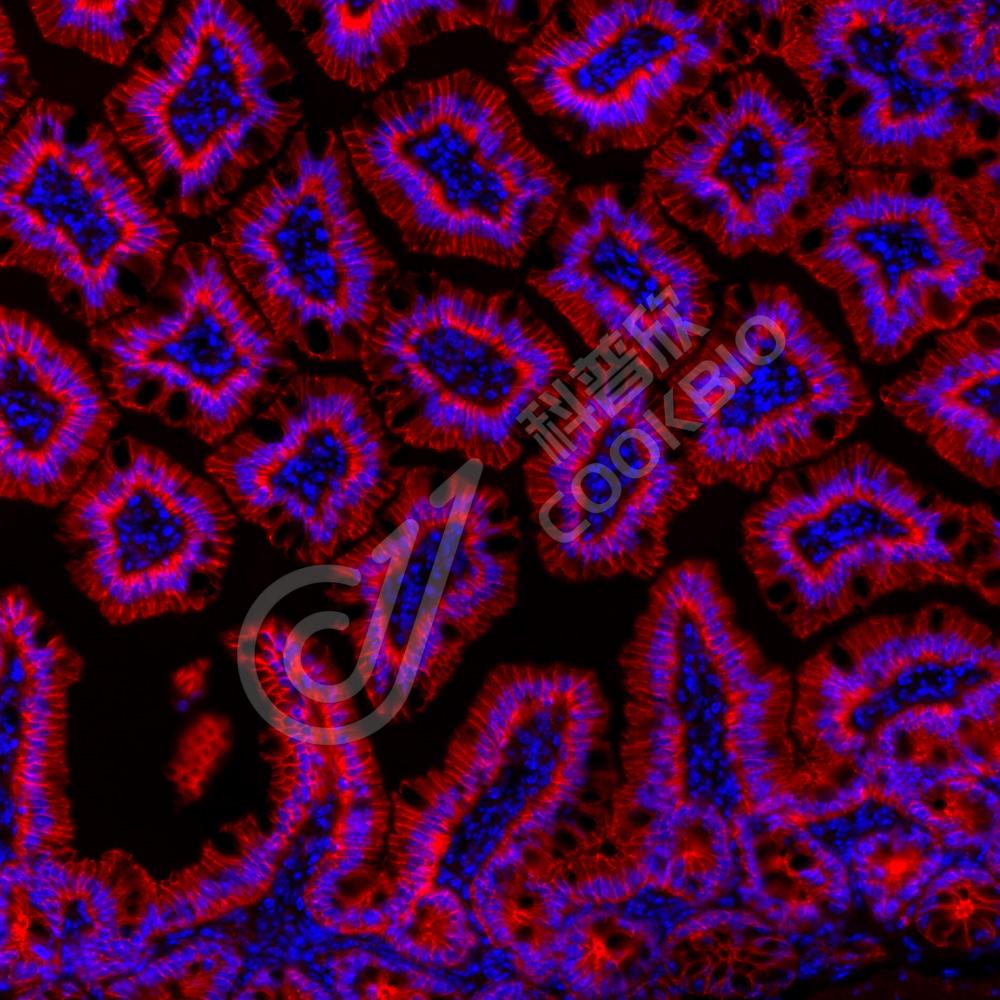

IF检测Occludin蛋白(货号 K1334203)(红色).

样品: 人肾, 4%多聚甲醛 (货号KSG1101) 固定12-24小时.

抗原修复: Tris-EDTA抗原修复液(pH 9.0) (KSG1203), 98℃, 20分钟.

封闭: 3% BSA(货号KSGC305010)的PBS溶液, 室温孵育30分钟.

—抗: 1: 1000稀释, 4℃ 孵育过夜.

二抗: Cy3标记山羊抗兔IgG (H+L) (货号KB63909), 1: 300稀释, 室温孵育1小时.